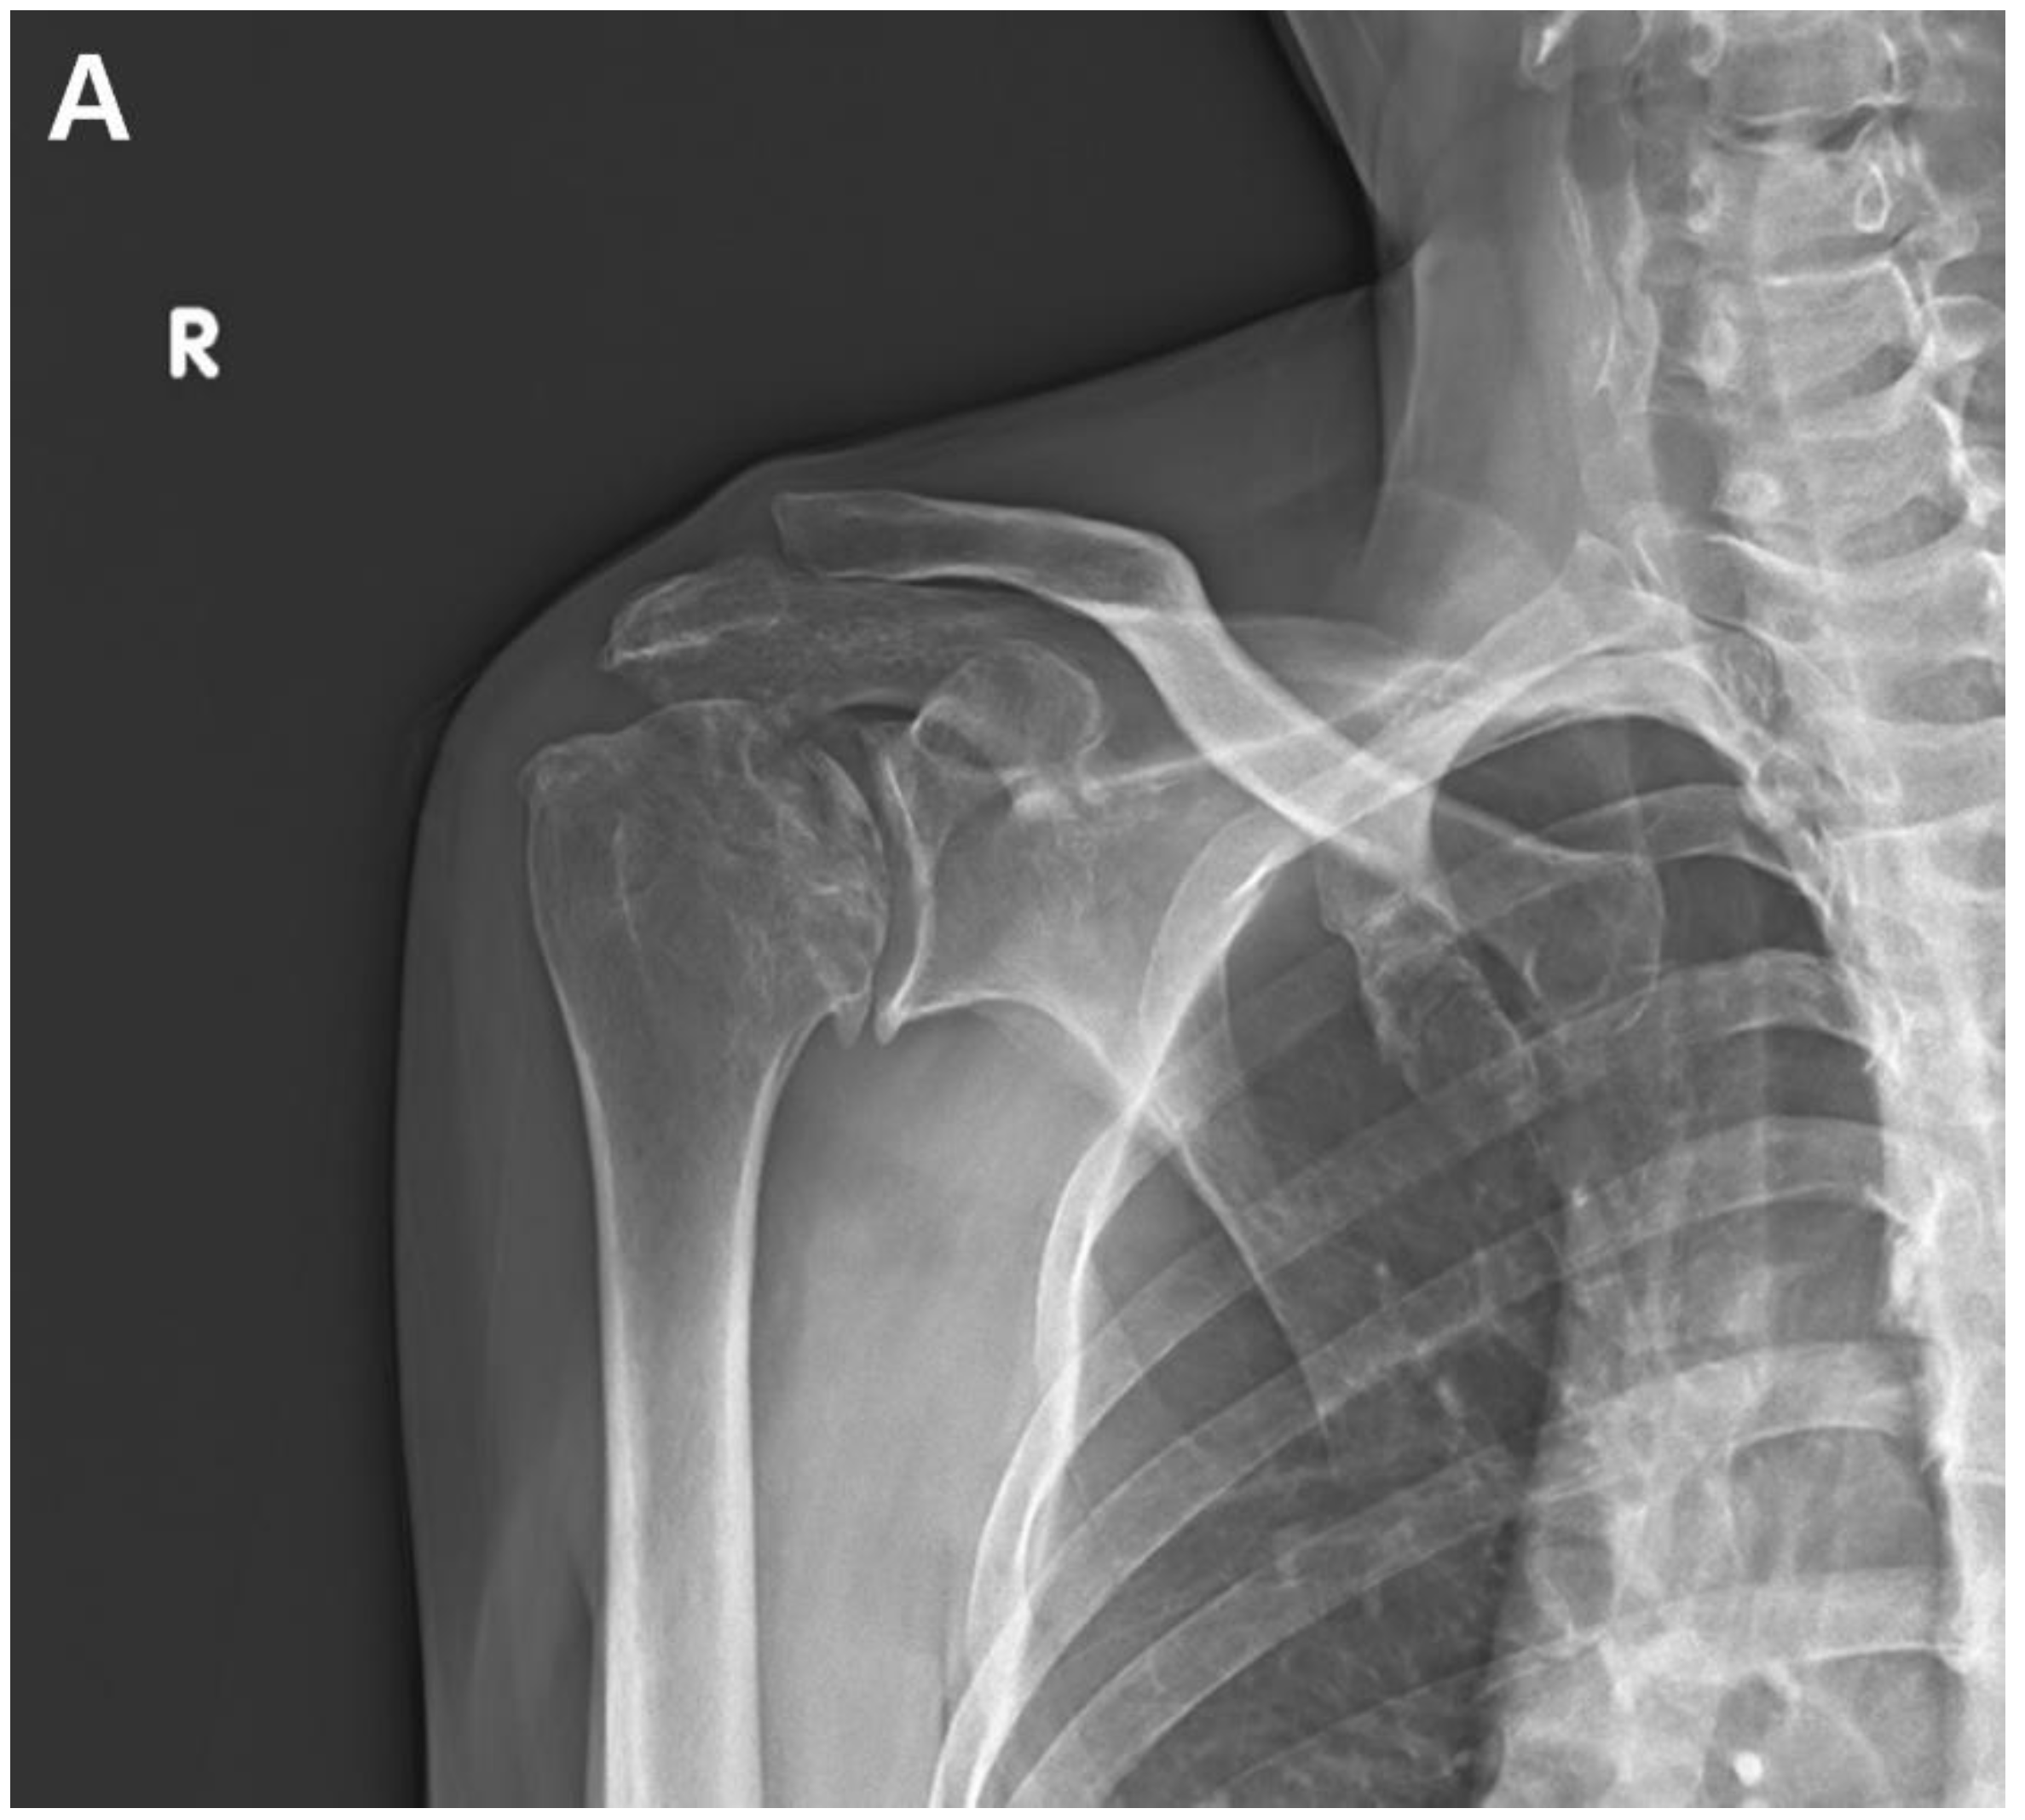

At 6-months postoperatively, functional outcomes were reported as a VAS score of 2, an ASES score of 79, and a CMS score of 75. Shoulder ROM was assessed as 135° forward flexion, 135° abduction, 70° external rotation, and internal rotation of the 10th thoracic vertebra. Radiographs showed an intact joint space and congruency (Fig. 3).

Figure 3. A. Immediate postoperative anteroposterior radiograph. B. Anteroposterior radiograph of the shoulder at 6-months postoperatively showed no significant change in the radiographic findings of the glenohumeral joint.